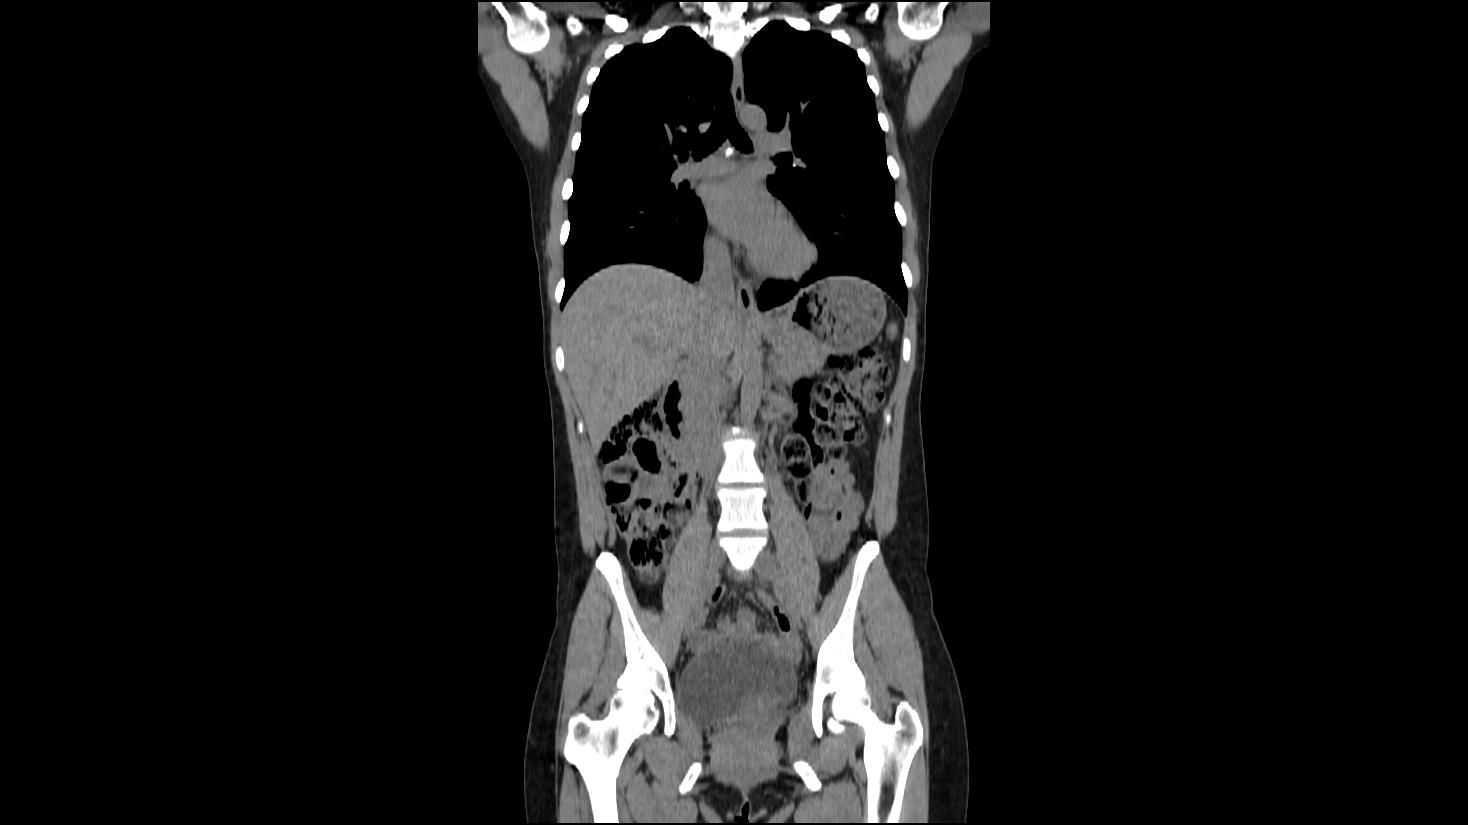

A Full Body Scan That Discovers Problems Before They Advance

A full body scan delivers a fast, detailed look at your internal organs, giving you insight into concerns that often grow unnoticed. This type of screening can reveal tumors, cysts, stones, inflammation, and other abnormalities that rarely cause symptoms in the early stages. Because many conditions progress quietly, full-body imaging is one of the most effective ways to stay informed and proactive.

With high-resolution CT imaging, your scan can uncover issues that routine exams, blood work, and physicals may overlook. You gain clarity about your health, the chance to address concerns early, and reassurance when everything appears normal.